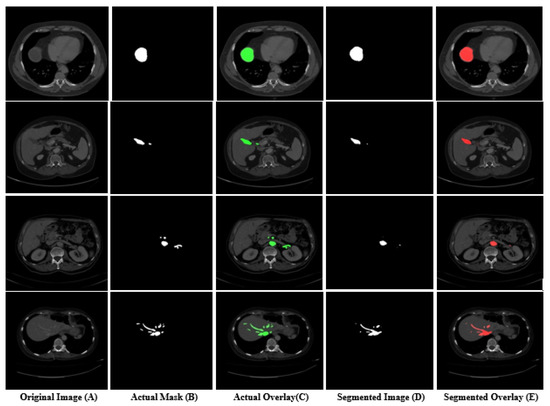

Moreover, some sample images that were segmented by our model are shown in Figure 6. In Figure 6, column (A) shows the original test set slice images, column (B) shows the actual masks of the tumor, column (C) shows the actual overlay results of the original mask over the image, column (D) shows the masks that were predicted by the model, while column (E) shows the predicted overlay results of a predicted mask on the images. It is observed from Figure 6 that the model found difficulty in segmenting very small tumors, as shown in the last row images. Similarly, the model also found difficulty in segmenting in the second row, as shown in columns (B) and (D) of Figure 6. All the scores were calculated with the help of predicted and actual masks, which are shown in columns (B) and (D) of Figure 6. Furthermore, the Dice and Jaccard scores of individual CT scan slices in the test set is shown in Figure 7. In Figure 7, the x-axis shows the number of CT scan slices, while the y-axis shows the dice and Jaccard score. It is observed from Figure 7 that, for most CT scans, the Dice score was above 80.

Figure 6.

Segmentation results of liver tumor from a CT scan using our proposed framework.